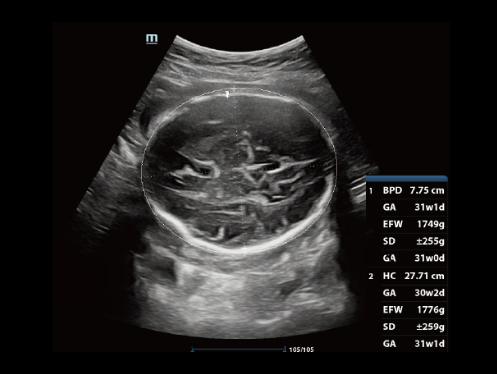

DC-80A con X-Insight mette a disposizione strumenti di una intelligenza eccezionale specifici per la cura della donna, dalla fertilit├Ā allo screening prenatale, e al post partum.

Immagini cliniche